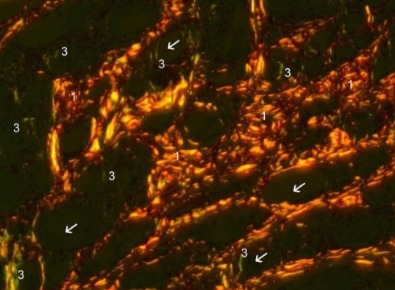

再生針的膠原蛋白增生效果,根據《Taylor & Francis》醫學文獻(下左圖圖說),使用PSR影像放大200倍顯示,CaHA附近(白色箭頭)反覆合成,產生大量的 I型膠原蛋白(橘紅色)及III型膠原蛋白(綠黃色)。右圖圖說:CaHA填充劑7個月後,仍觀察到豐富的III型膠原蛋白新生,且纖維形狀各異,從粗而緻密、到非常細的III型膠原纖維都有。